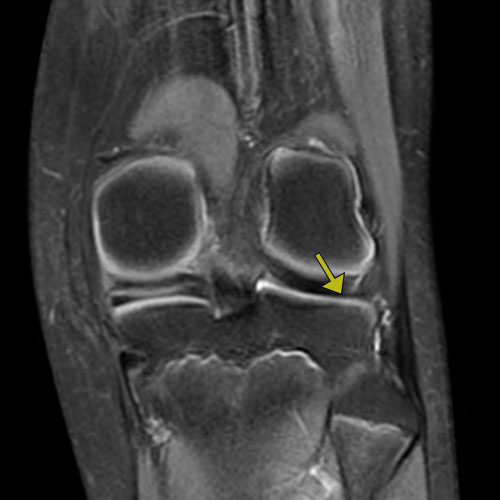

Aşağıda verilen sol diz MR görüntüsünde ok ile işaretli anatomik yapı aşağıdakilerden hangisidir?

Cevap: C) Meniscus lateralis Açıklama: Diz eklemi MR görüntülerinde menisküs yapıları, femur ile tibia arasında yer alır ve iki temel parçadan oluşur: medial menisküs ve lateral menisküs. Eğer görüntüdeki ok işareti dizin dış kısmına yakın bir bölgeyi işaret ediyorsa, bu yapı büyük olasılıkla Meniscus lateralis olarak adlandırılan dış menisküs olacaktır. Meniscus lateralis, dizin dış kısmında, medial menisküs ise dizin iç kısmında yer alır. Bu bağlamda, işaretlenen yapı dizin dış kısmında görüldüğü için doğru seçenek C) Meniscus lateralis olarak belirlenmiştir.